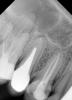

diesel87 Опубликовано 14 апреля, 2013 Поделиться Опубликовано 14 апреля, 2013 Помогите правильно трактовать снимок, история такова: пришла пациентка из другой клиники, говорит только из нее, там сказали что нужно удалять 16 зуб, но удаление сложное и они за него не возьмутся и говорит отношение плохое к пациентам...ну ладно думаю, посмотрю, по факту 16, 15 - под пломбами, перкуссия болезненна, идем на снимок, а там как мне показалось что киста не одонтогенная, по крайней мере щели корней 15 и 16 целые, а прям над ними в пазухе я заподозрил кисту, спрашиваю насморка есть? Да говорит, справа, пару дней как, а болит спрашиваю давно, как раз говорит пару дней и болит...и тут еще одно звено цепочки замкнулось в голове...Вообщем отправил ее на ОПТГ сегодня, завтра придет и у нее еще есть полугодовалый ОПТГ, посмотрю, сравню...А вы гляньте на прицельный, рассудите меня, спасибо. Ссылка на комментарий

als00 Опубликовано 15 апреля, 2013 Поделиться Опубликовано 15 апреля, 2013 (изменено) Медиальный щечный корень шестого не запломбирован.( впрочем и остальные плохо обтурированы). Над ним процесс. Он и может быть проблемой в пазухе. Совсем не редкость Изменено 15 апреля, 2013 пользователем als00 1 Ссылка на комментарий

SergioS Опубликовано 15 апреля, 2013 Поделиться Опубликовано 15 апреля, 2013 Воспаление на всех корнях 16. 15 и 14 тоже надо перелечивать.Как ранее было сказано, ОПТГ не дает четкого представления о наличии корней или процесса в пазухах.Отправляйте на КТ. Ссылка на комментарий

777white Опубликовано 15 апреля, 2013 Поделиться Опубликовано 15 апреля, 2013 Воспаление на всех корнях 16. 15 и 14 тоже надо перелечивать.Как ранее было сказано, ОПТГ не дает четкого представления о наличии корней или процесса в пазухах.Отправляйте на КТ.+1Может киста на медиальном корне, имеет вестибулярное положение Ссылка на комментарий